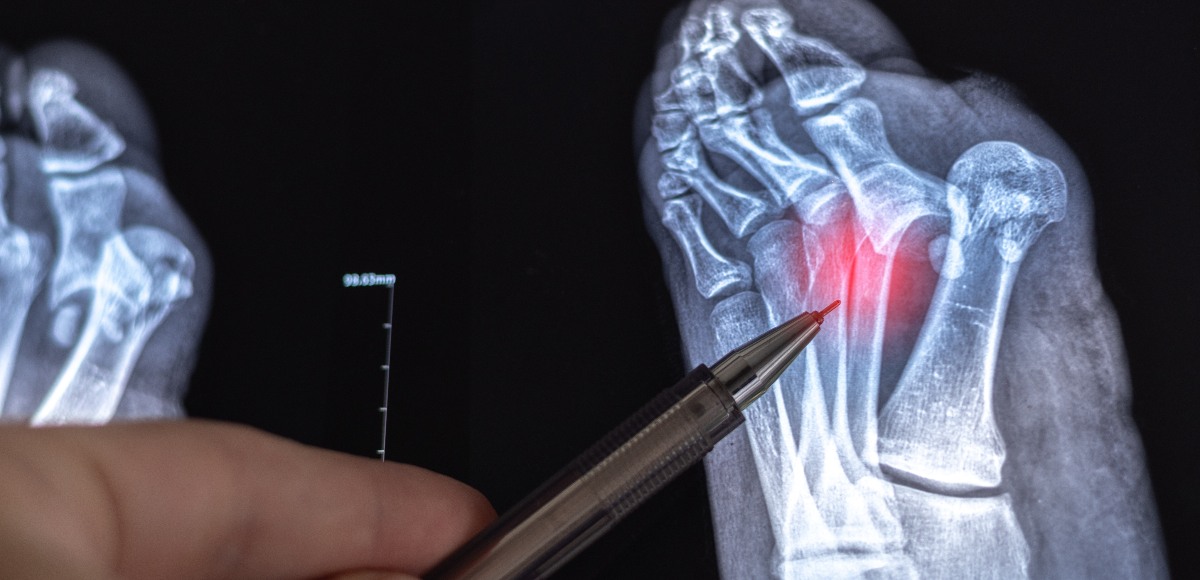

La radiografia del piede: cos’è, cosa si vede e quando farla

Una radiografia al piede può essere utile per diagnosi, controllo e prevenzione delle patologie che colpiscono il piede